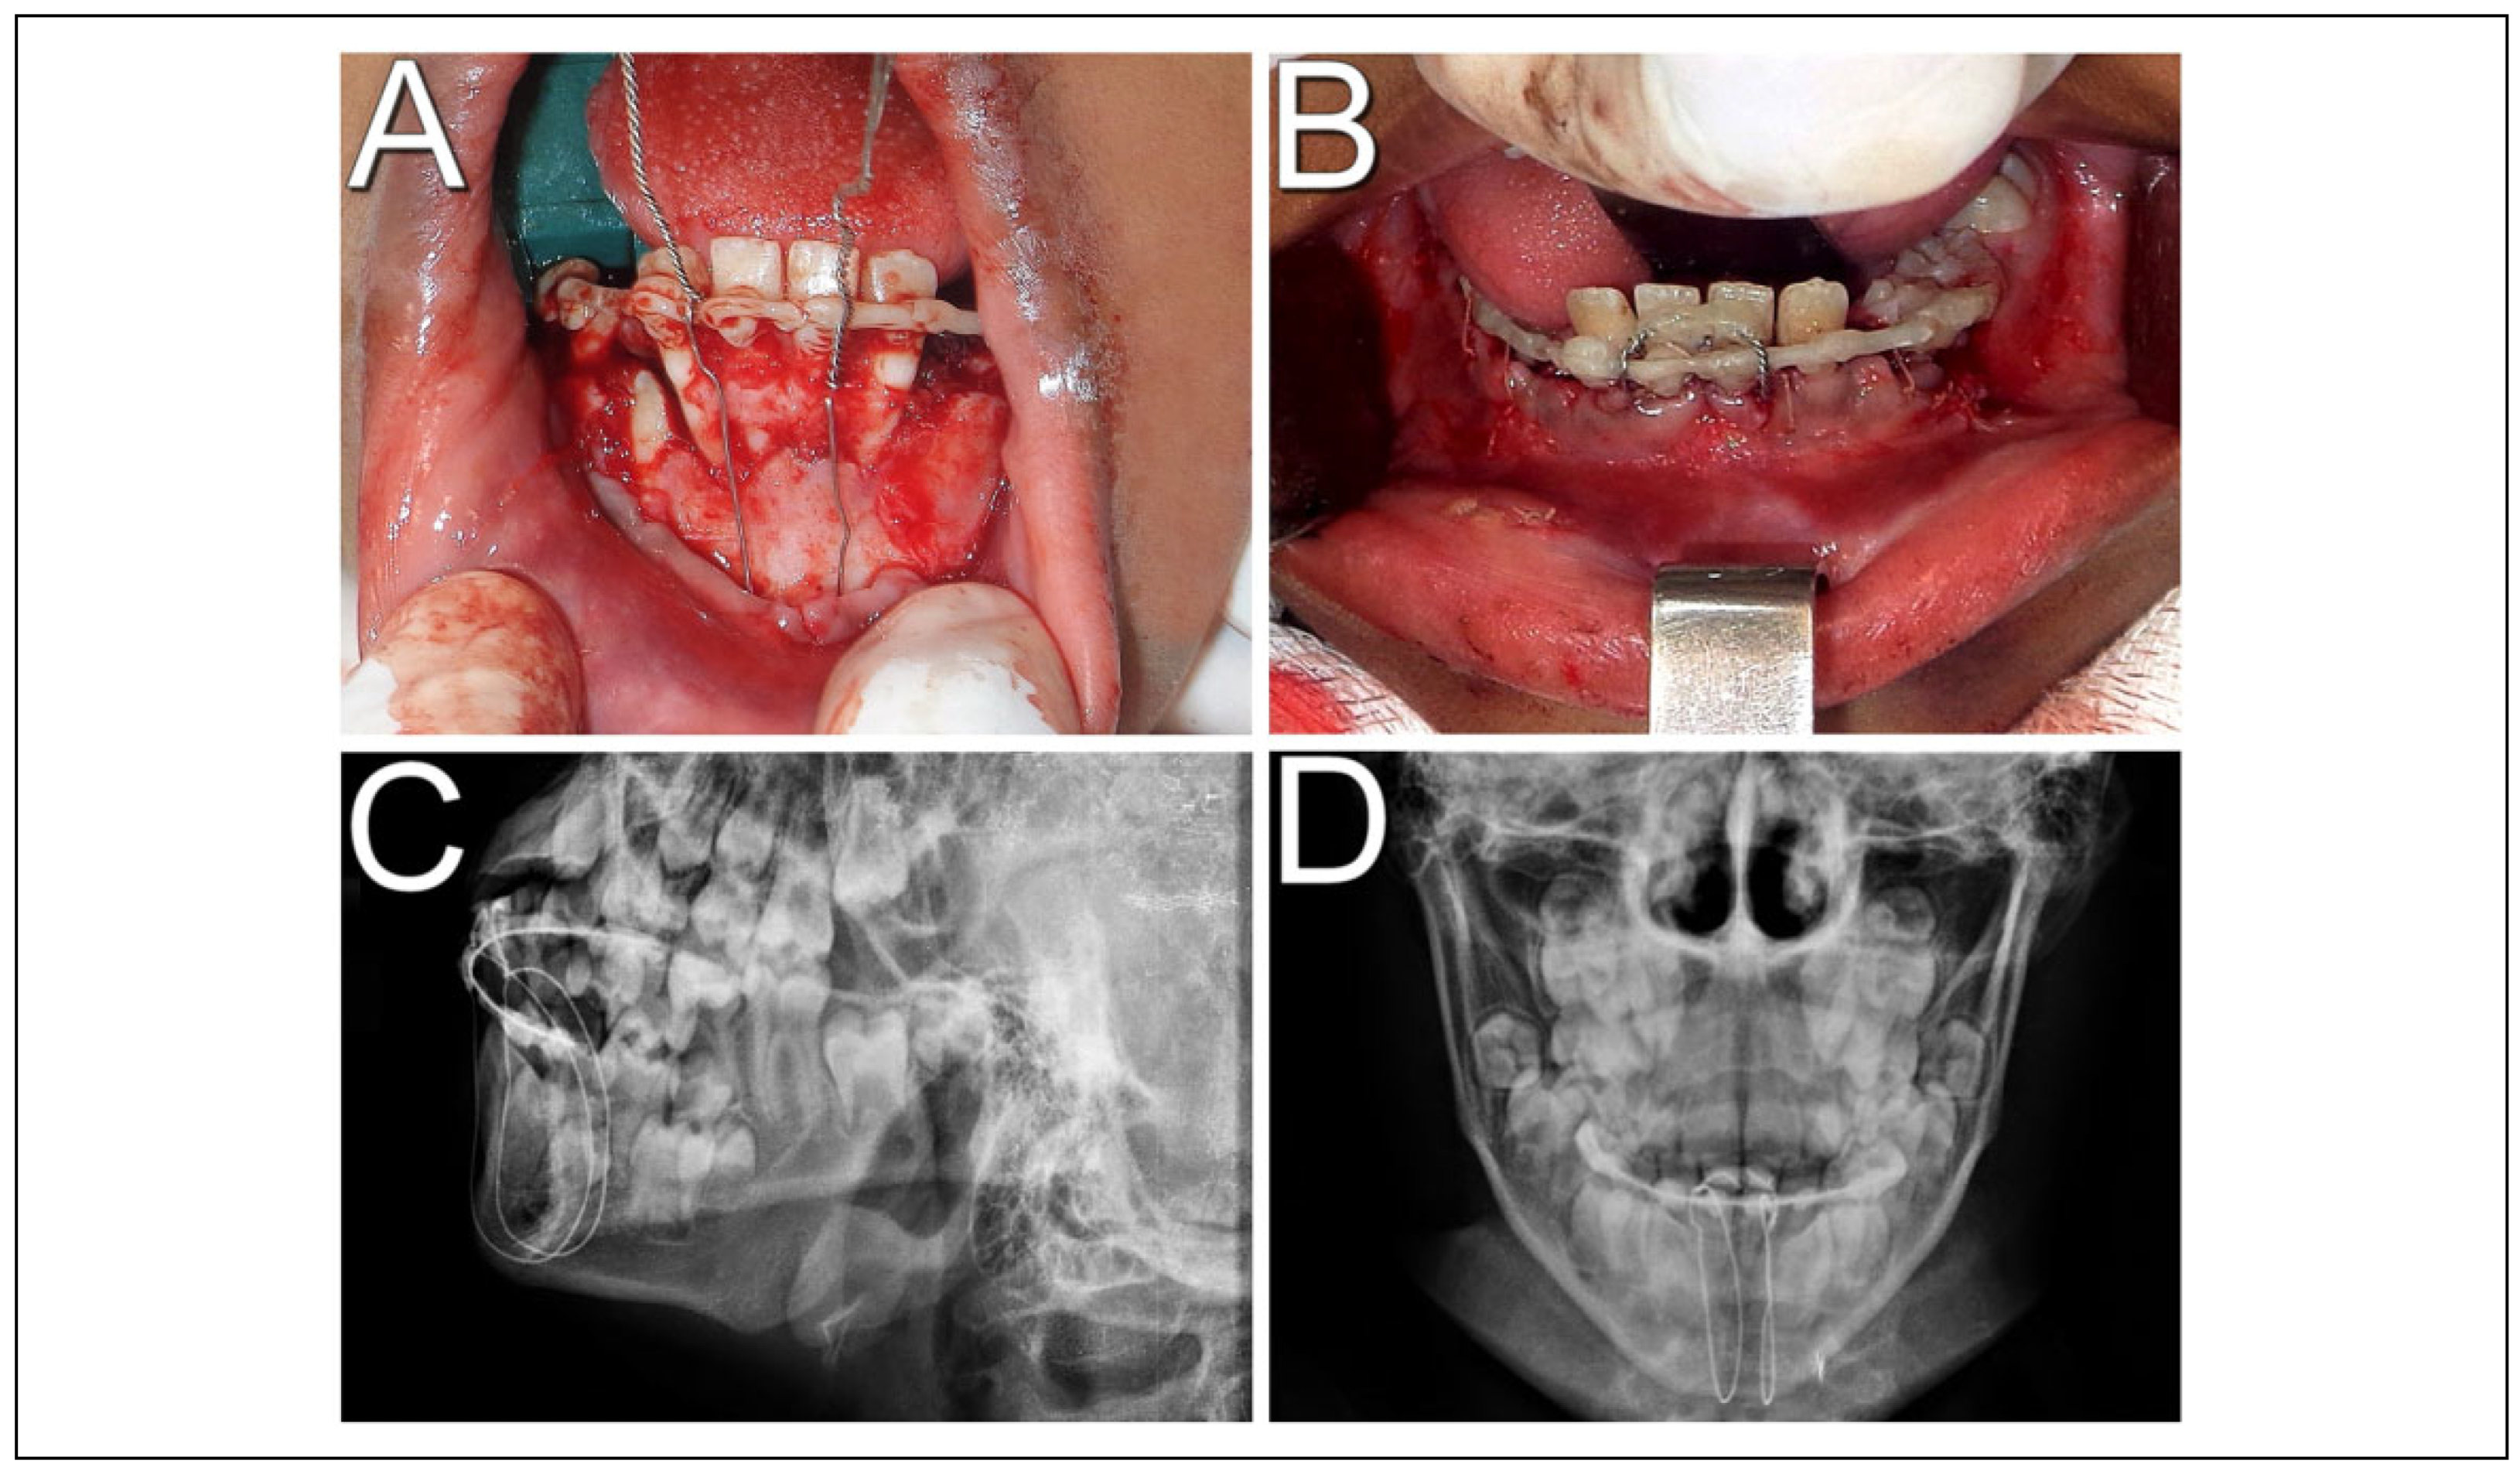

In the 90-day follow-up, semi-rigid splinting and bone cerclage were removed under local anesthesia (Figure 3). The lower incisors evolved with improvement in both stability and mobility. In pulp vitality test, the teeth involved responded negatively, proceeding to the beginning of root canal treatment. However, the patient did not attend the consultations regularly, not finishing the endodontic treatment. In the 4-month postoperative period he returned with an abscess in the submental space (Figure 4), with a root canal disinfection and medication of the affected teeth being performed, in addition to antibiotic therapy with Amoxicillin 500 mg every 8 hours for 7 days. The patient evolved with regression of the infectious condition, and in the 9-month postoperative period he exhibited stable occlusion, teeth without mobility, endodontic treatment completed and without signs of infection (Figure 5). Currently, he is being followed up for 3 years and 6 months, with satisfactory clinical and radiographic results (Figure 6).

Figure 3. Ninety-day follow-up. (A) Intraoral image after removal of steel wires and dental splint; (B) periapical radiography of lower incisors prior to circummandibular wires removal; (C) periapical radiography after removing the steel wires.